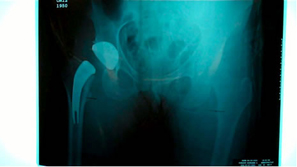

Intra-operative x-ray helps check mechanical alignment and modular features allow for last minute fine tuning. Neck length adjusted. Stem fit like a custom implant. 2 prox x 10 mm. |

Trial neck off the final implant then 8 mm varus neck was chosen for final implantation.

Pt. doing well first day post-op. Saving all the lateral structures was very impressive.

Obvious as we new there would be outliers this first case confirms Australian experience that a smaller size may be needed and would more than likely be a monoblock neck design.

In both of these cases with tight fit cortical bone needs to be shaped to fit the medial curve and preparations for the differential size between the rasp and implant with the T-back. More experience is needed but possible additional preparation for the definitive stem in very tight situations may need to be addressed. Over all impression was good and basic instruments work well and the initial stability of the implant is impressive.